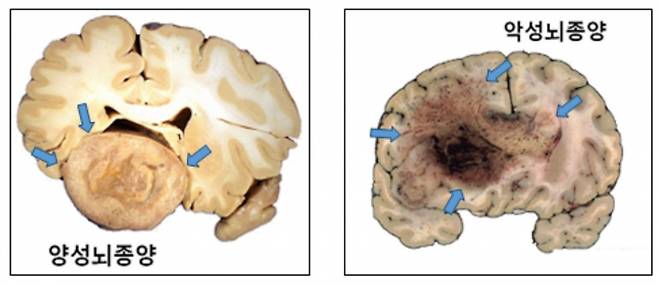

뇌종양은 조직학적 특성에 따라 '양성'과 '악성'으로 나눈다. '양성 뇌종양'은 성장 속도가 1년에 2㎜ 미만으로 느리다. 주변 부위와 비교적 명확히 구분되기 때문에 수술을 통한 완치 가능성도 높다. 종양의 크기·위치에 따라 일상생활이 불편할 수 있어도, 5년 생존율이 90% 이상일 만큼 생명에 거의 지장이 없다. 따라서 별다른 증상이 없는 경우 경과 관찰만 하며, 증상이 있거나 주기적으로 MRI(자기공명영상)를 촬영하며 관찰하다가 성장 속도가 일반적인 경우보다 빠르다고 판단될 때 치료를 고려해도 늦지 않다.

'악성 뇌종양'은 진행이 빠르고, 성장하면서 뇌 조직을 침범하는 경향을 보인다. 뇌교종이 대표적이다. 뇌교종은 뇌신경세포를 지지하는 교세포에서 발생하며, 절반 이상이 악성이다. 양성 뇌교종도 시간이 지나면서 악성화되는 경우가 많다. 뇌교종이 발견되면 일부 예외적인 경우를 제외하고, 대부분 증상이 없더라도 치료가 필수적이다.